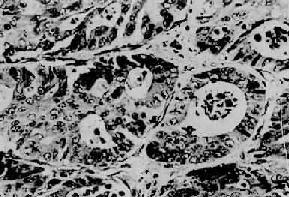

1.隆起型 肿向肠腔内突出,又可分为隆起息肉型(图10-29)及盘状型两个亚型。镜下多为分化成熟的腺(图10-30)。

直肠腺<a href=癌"/>

图10-30 直肠腺

细胞分化较好,巢大多呈腺样结构(Ⅱ73-3057)